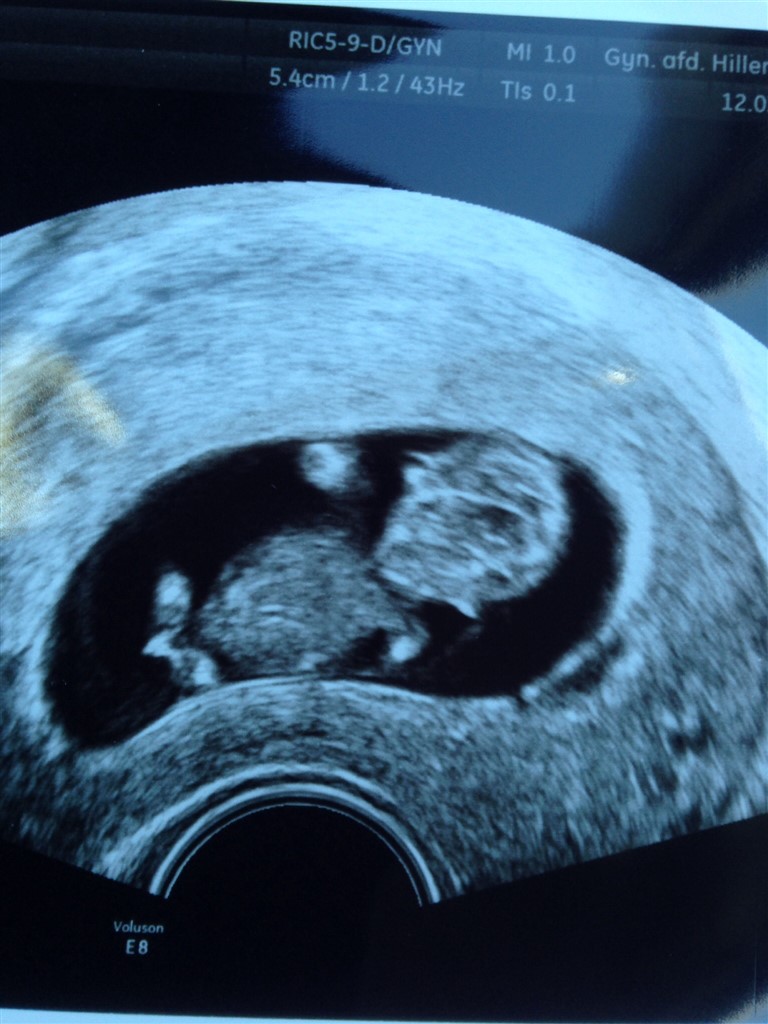

10+3 og 4 cm livlighed

Har i dag været til scanning på gyn.amb. som led i det kontrolforløb jeg har været i efter min mola før jul. Med hjertet i halsen som de andre gange, lagde jeg mig på briksen til en indvendig scanning... Og tak skal du have en lille livlig Spunk der sprællede for fuld hammer  Jeg er så glad, og lettet over at alt mod alle odds, er helt perfekt og jeg nu kan følge et normalt svangerforløb